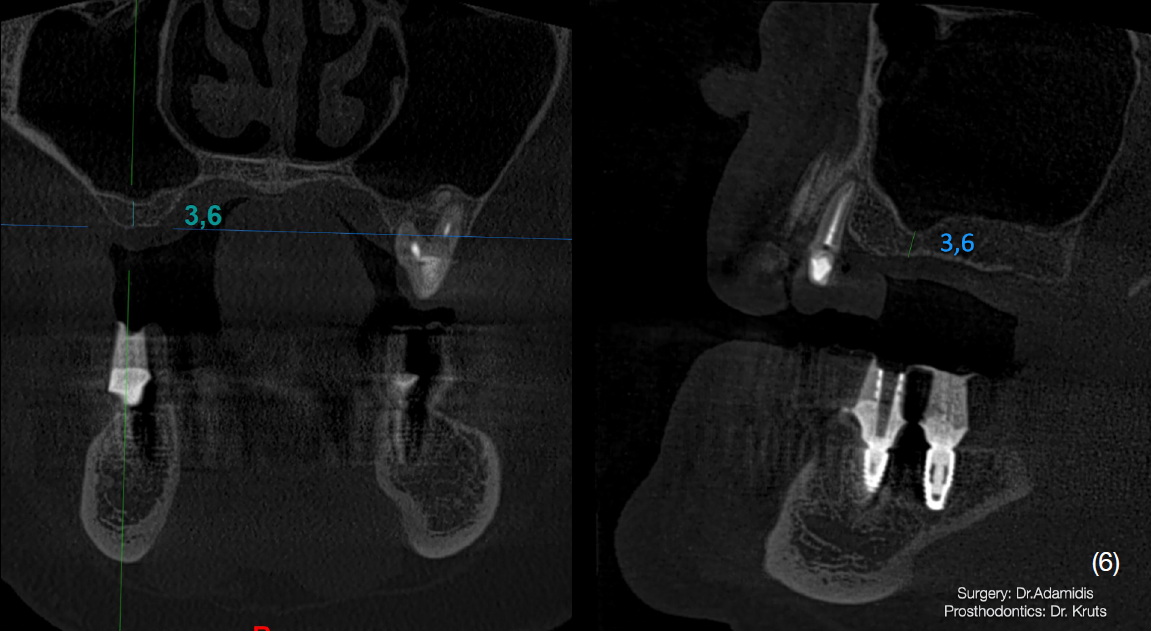

Після детального вивчення даних комп’ютерної томографії пацієнта, було затверджено план лікування, який складався із двох хірургічних етапів.

Через 3 місяці після першого етапу було проведено операцію на верхній щелепі. Було виконано відкритий синус-ліфтинг в першому квадранті та закритого в другому.

Матеріалом, що використовувався під час операції був Straumann Xenograft та аутологічна кістка, яка була забрана із ділянки зовнішньої косої лінії.

Одномоментно з кістковою аугментацією встановлено імплантати Strauman BLT діаметром 3.3mm в ділянках 12, 15, 17, 23, 25 зубів. Операційну рану було ушито, зворотньо зафіксовано тимчасову конструкцію на наявних зубах.